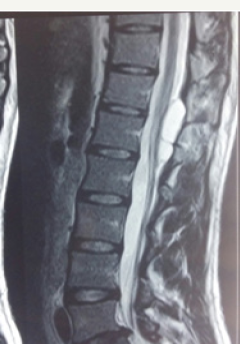

Figure 1b: Pre-operative T2 weighted sagittal MR images showing CSF intensity lesion at d11-d12 level.

19 year male presented with a history of lower back pain of 6 months duration. It was insidious in onset, gradually progressive with mild weakness of both lower limbs. He had a past history of fall from a tree with sustained injury to back 10 years ago. On examination, he had paraparesis with power (grade 4/5). There were no bladder and bowel disturbances. Other physical findings were not remarkable. MRI dorsal spine with screening of the entire spine showed a small, elongated, well defined CSF signal intensity extradural cystic lesion at D11-12 level suggesting arachnoid cyst. The lesion was compressing the dorsal spinal cord from behind (Figure 1a-1c).

The patient improved symptomatically in post-operative period. Follow up MRI was done 1 month after surgery showed complete disappearance of the cyst (Figure 2).

Figure 2: Follow up T2 weighted MR Image taken 1 month after surgery showed complete disappearance of the cyst.

Magnetic resonance imaging appears to be effective as an initial modality for diagnosing arachnoid cysts and does not require the intrathecal injection of contrast medium. It can define the anatomical relationship to surrounding structures. The imaging characteristics of arachnoid cysts are similar to those of CSF signal intensity. Epidural fat capping of the lesion at its superior and inferior poles can be seen on sagittal T1-weighted MR images, which further suggests its extradural location. The presence of vertebral body scalloping and expansion of the neural foramina bilaterally from osseous remodelling suggests a longstanding mass effect from the lesion.